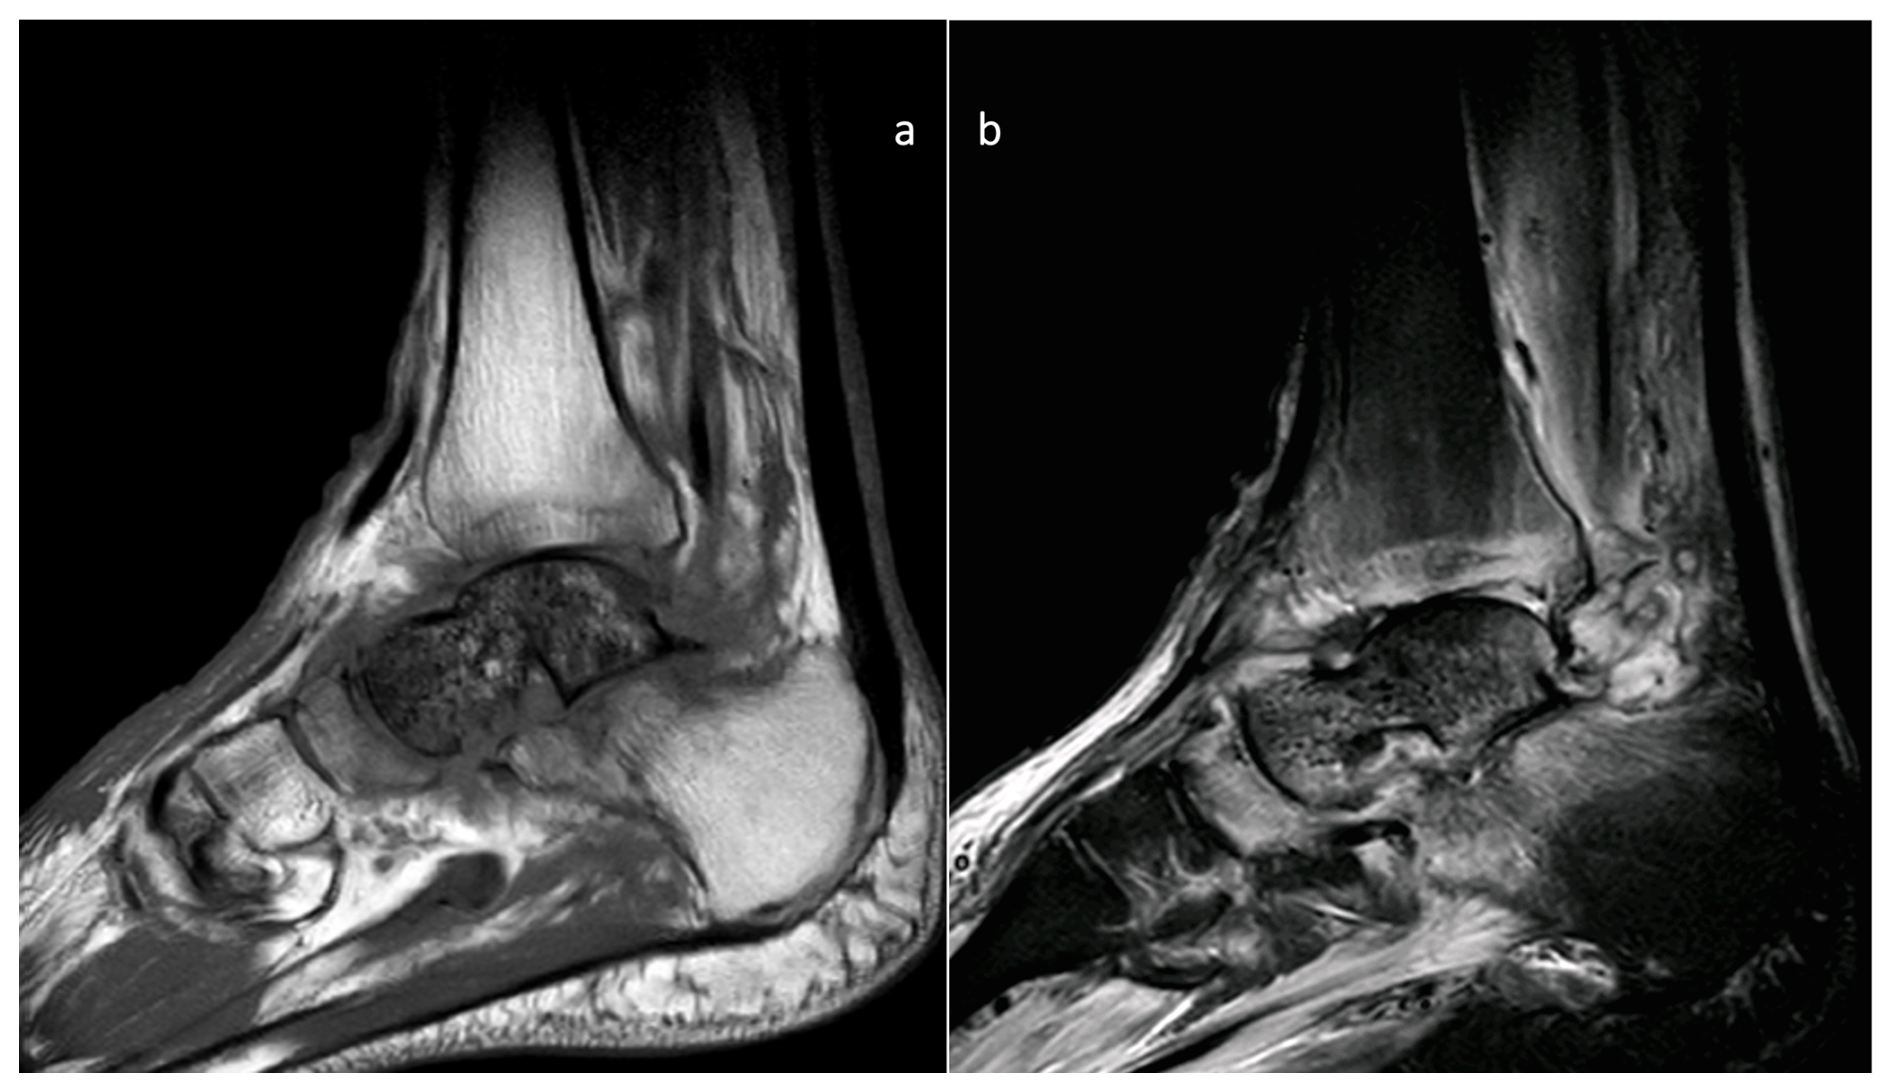

In November 2019, the infection relapsed; at this point, he was referred to our hospital. The flap was in a good condition, with some erythema around it. MRI confirmed AVN and FRI with no other bones involved or purulent collections (Fig. 2).

https://jbji.copernicus.org/articles/10/419/2025/jbji-10-419-2025-f02

Figure 2MRI images of the preoperative state of the talus. Sagittal MRI images showing signs of avascular necrosis and osteomyelitis: (a) T1 and (b) STIR images.